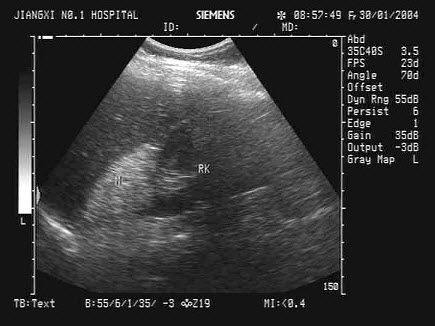

32、单项选择题

根据超声声像图,提示为()

A.肾下垂

B.肾发育不良

C.异位肾

D.马蹄肾

E.游走肾